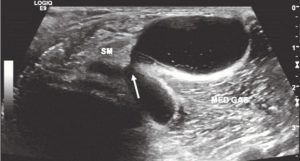

Baker Cyst

A Baker cyst demonstrates a good example of multiple echotextures observable with ultrasound. Also known as the semimembranousus (SM) medial gastrocnemius (MED GAS) bursa, a Baker cyst is a communicating bursa which means that it forms when there is a large intra-articular effusion in the knee that “leaks.” Note in Figure 1 the neck of the Baker cyst as the fluid comes out between the SM and MED GAS tendons.